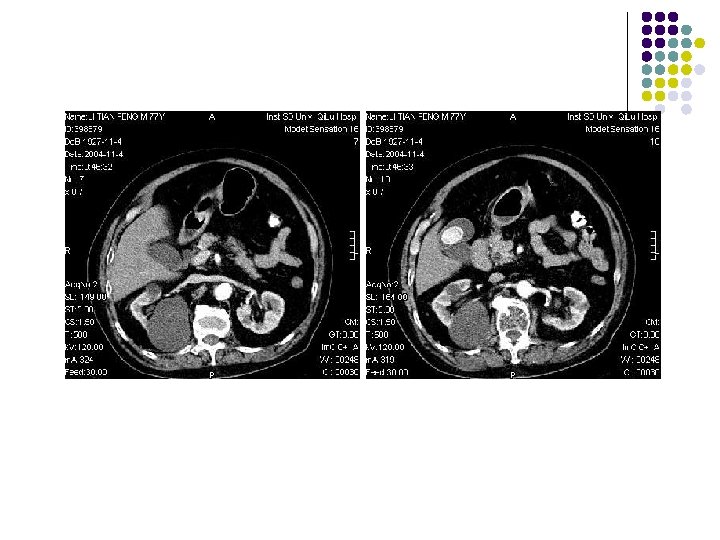

CT Modern multidetector computed tomography is a new diagnostic imaging tool that allows multiplanar reformation. CT cholangiography performed with 64 channel multidetector. CT scanners could provide much more information regarding the biliary tree and its abnormalities.

Imaging Techniques l l l CT scans were obtained on a 64–channel helical CT scanner with the following parameters: 0. 5 seconds per rotation, 5 -mm collimation, pitch of 0. 984: 1, and tube current of 120 k. V per 300– 400 m. As. Transverse 0. 625 -mm-thick sections were reformatted into thinsection coronal images, maximum- intensity-projection (MIP) images, and volume- rendered (VR) images. An intravenous drip infusion of 100 m. L of meglumine iotroxate (Biliscopin; Schering, Berlin, Germany) is administered for 50 minutes as a biliary contrast agent 40– 60 minutes prior to scanning. This biliary agent has been approved in some countries, including Japan, and has been used for tomographic cholangiography.